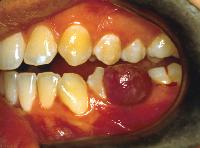

The pyogenic granuloma is a relatively common, tumorlike, exuberant tissue response to localized irritation or trauma. The name pyogenic granuloma is a misnomer since the condition is not associated with pus and does not represent a granuloma histologically. It is a reactive inflammatory process filled with proliferating vascular channels, immature fibroblastic connective tissue, and scattered inflammatory cells. The surface usually is ulcerated, and the lesion exhibits a lobular architecture.

Before